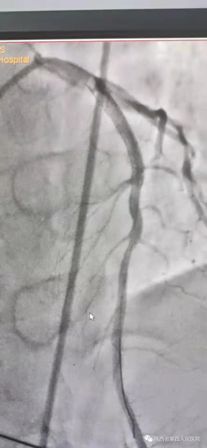

(术前造影) (术后)

11月10日15时58分左右,家住医院附近的中年男性辛先生在家人陪伴下来到我院急诊内科门诊诊室,满头大汗,捂着胸口说胸痛、胸闷、气短,急诊科主治医师钟高亮立即安排床位进行留观给予吸氧、心电监护、查体,心电图提示:1、窦性心律;2、室性早搏;3、急性下壁、前壁心肌梗死,诊断:急性冠脉综合征、心肌梗死。随后患者在急诊科留观室病情突然加重,意识丧失、四肢抽搐、面色苍白、全身大汗、呼吸急促,心电监护提示心室颤动,判断其可能为急性心肌梗死心源性休克,急诊科和心内科医生立即行胸外心脏按压,电除颤三次等对症治疗,立即启动胸痛患者抢救应急预案,开启绿色通道,和患者家属谈话,为其迅速办理入院手续,给予升压补液扩容等抢救治疗,积极完善术前准备,联系医务科和介入导管室,于16时22分将患者转运至导管室,心内科主任、主任医师王选琦带领团队副主任医师孙耀林、王崇振,主治医师马艳萍共同夺取患者最宝贵生命时间,为患者选择了从下肢股动脉穿刺造影,从穿刺到开通血管用仅仅只用了十一分钟。16时33分顺利完成PAG PCI支架植入术后成功再通,患者转危为安,随后入住心血管内科CCU病房继续治疗。